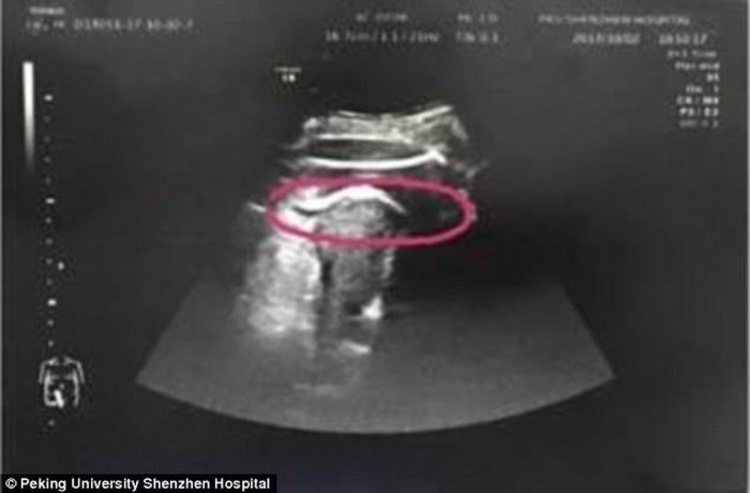

Sra. Zhang, sentiu por horas fortes dores abdominais e decidiu procurar ajuda médica e descobriu algo bizarro. O caso aconteceu em Pequim.

De acordo com o site Mega Curioso, na 35ª semana de gestação, seu bebê havia rompido o útero com sua perna e precisou passar por uma cesárea de emergência.

Zhang descobriu em 2016, fibroma em seu útero, que é uma espécie de tumor benigno, mas que precisa ser retirado por cirurgia. Após relatar isso aos médicos, os especialistas acreditam que o bebê acertou o local no útero em que era localizado o fibroma e, por conta disso, rompido o órgão da mãe aproximadamente 7 cm pelo chute. é aconselhável que as mulheres esperem até dois anos para engravidar após a retirada de um fibroma, mas Zhang foi pega de surpresa pela gestação.